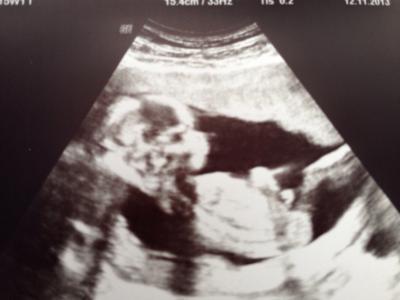

Bildchen vom Goldschatz ;-)

Hallo alle zusammen, war letzte Wo außerplanmäßig beim Facharzt, da ich immer wieder mal Blutungen habe und etwas beunruhigt bin. Es sind mittlerweile schon 2 Hämatome :-( aber dem kleinen Piepmatz im Bäuchlein schient es sehr gut zugehen, was auch das wichtigste ist. Hampelt was das Zeug hält und macht mich damit natürlich sehr glücklich. Ein Bildchen gab es auch, Wahnsinn wie gut man alles erkennen konnte, auch die Beinchen sind schon recht lang. Ach ich bin so stolz und hoffe das sich die Hämatome bald resorbieren und ich es dann sorgenfrei genießen kann bis zum Mai. Alles gute an die komplette Busmannschaft.., Lg luluuu

schön das dem bauchzwergi gut geht :0) wie groß is das kleine jetzt?

Sie hatte es da gar nicht gemessen, denk mal so um die 10cm oder?! Ist auf jeden fall zeitgerecht entwickelt. Termin bleibt Anfang Mai ;-)